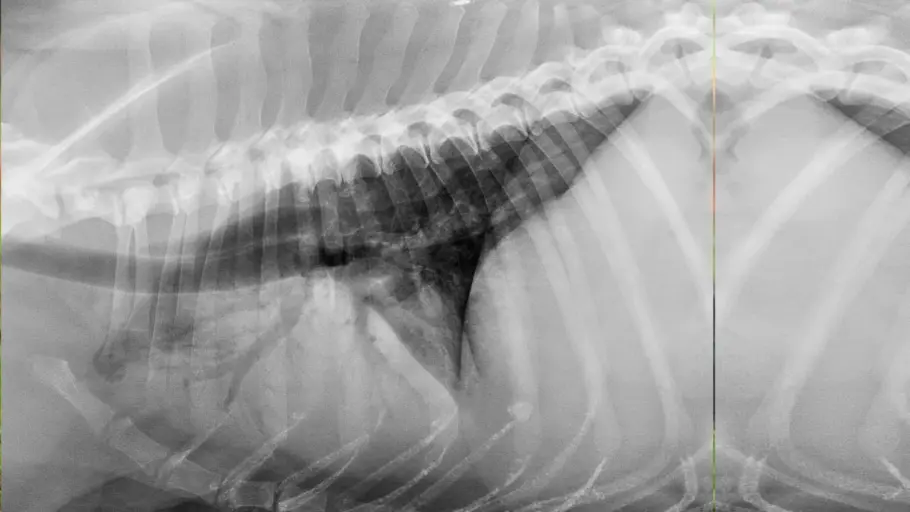

Para chegar ao diagnóstico, o veterinário faz a anamnese do animal com ajuda do tutor, exame físico completo para detectar possíveis sinais clínicos e identificar doenças secundárias. O especialista pode ainda solicitar exames complementares como hemograma completo, radiografia e ultrassonografia torácicas, ecocardiografia e mensuração de proteínas séricas. Este último permite avaliar o estado nutricional e detectar doenças renais, hepáticas e hematológicas.